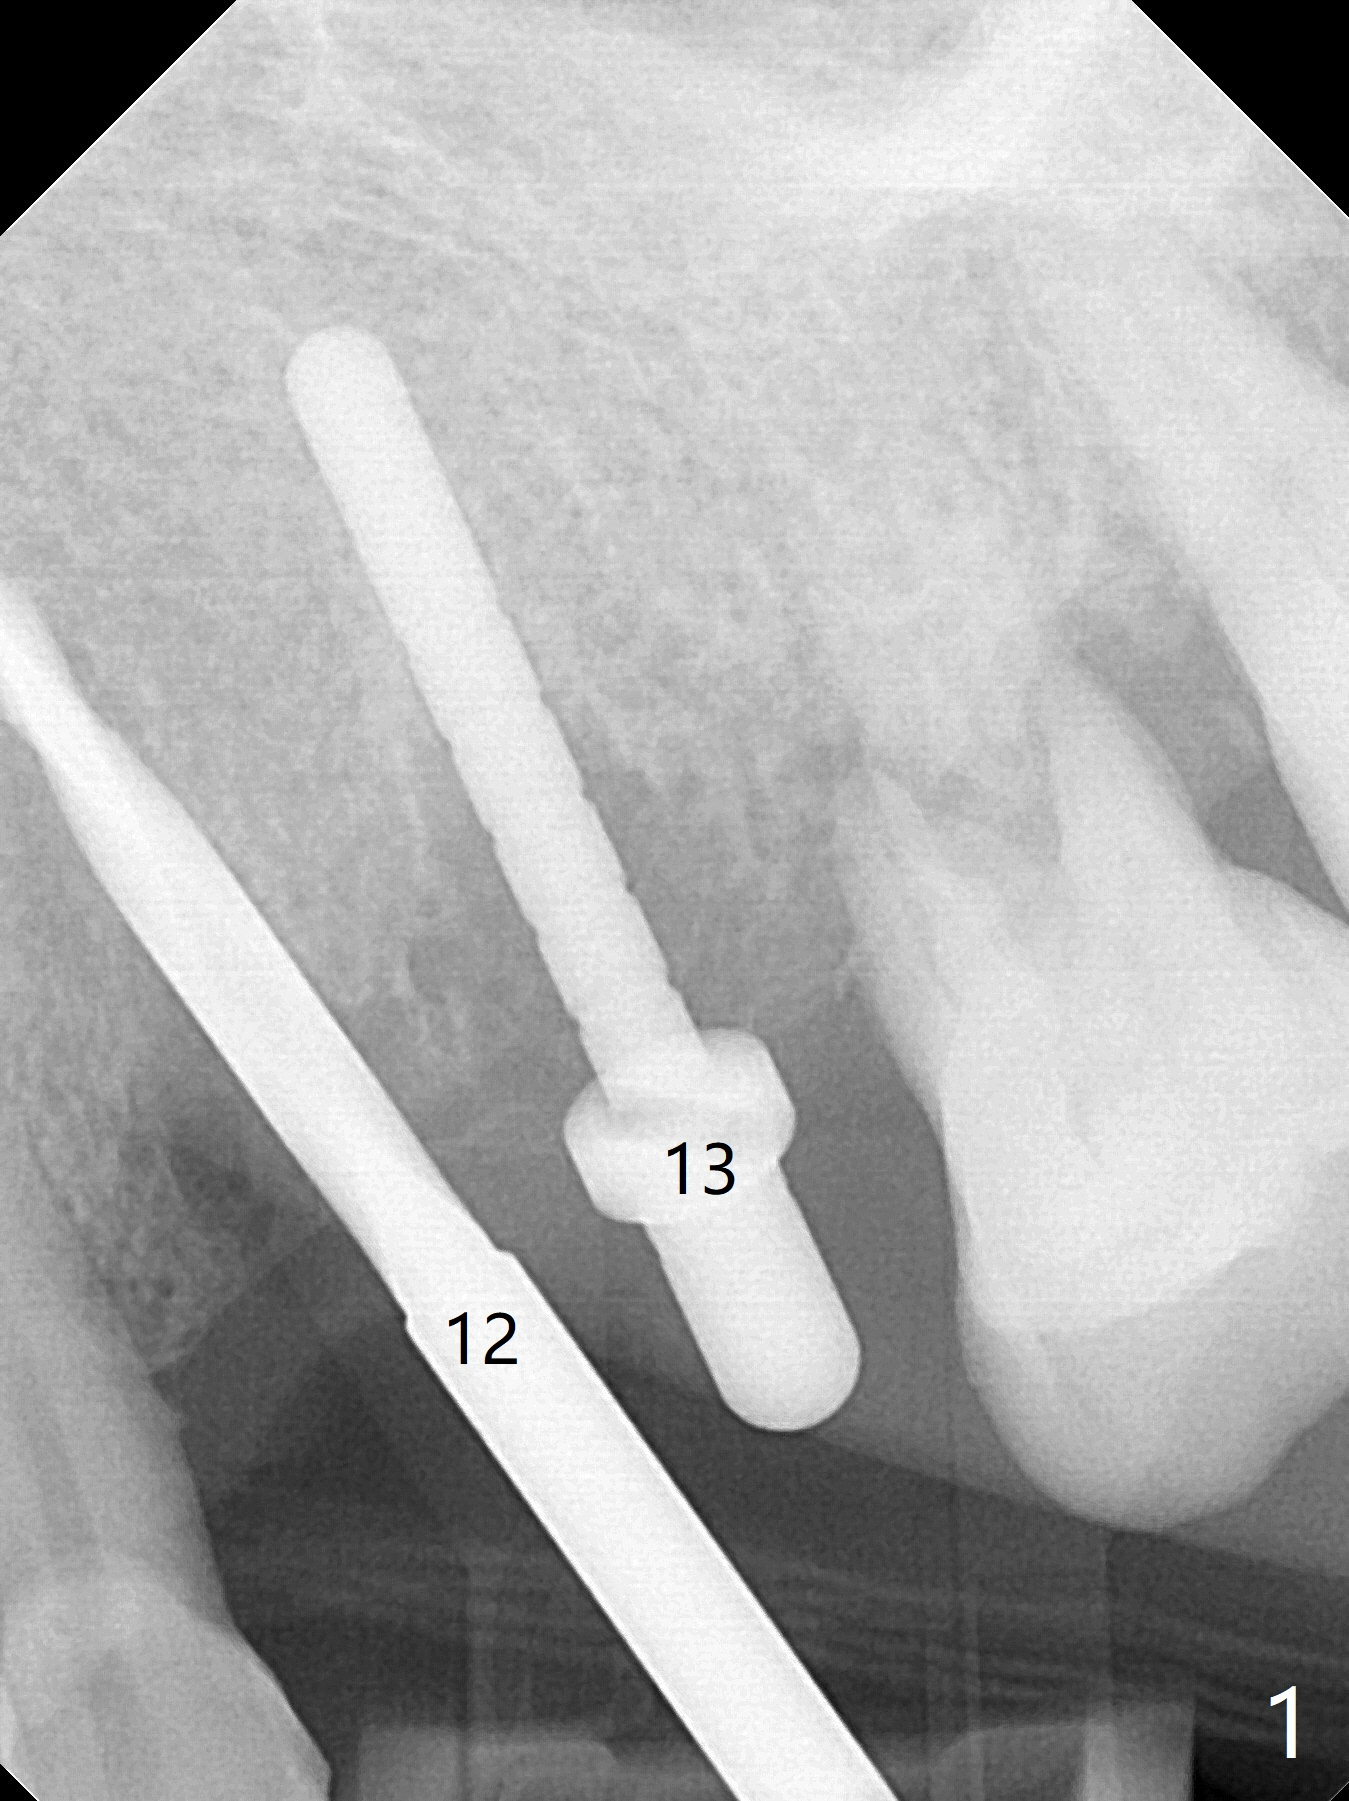

A 66-year-old woman returns to office requesting implant placement at #12 and 13 at an appointment supposed for #5 impression. Depth of osteotomy is 20 mm (gingival level, Fig.1 ( 2mm)). After correction of trajectory at #12 and 3 mm drill for 16 mm at the sites, two of 3.8x16 mm implant are placed with insertion torques of 35 and 15 Ncm, respectively (Fig.2). Before and after change into shorter abutments (4.5x4(4) and (5)), Vera Graft is placed (Fig.3 *). To increase stability, either increase the diameter (4 (Fig.4 at #5) or 4.5 mm instead of 3.8) or length of the implants (red dashed line: sinus floor). Or use dummy implants. The allograft appears to have been incorporated into the host bone nearly 4 months postop (Fig.5). The abutment of the isolate implant at #5 becomes loose twice (Fig.4). To reduce the chance of abutment loosening at #12 and 13, can you make splinted crowns? If the two separate crowns have been fabricated, can you make a slot (with light undercut) in the proximal area of each crown (Fig.6 (occlusal view): S) in addition to access hole (A)? After cementation, composite will be placed in the slots (lock) so that the crowns will not rotate and become loose.